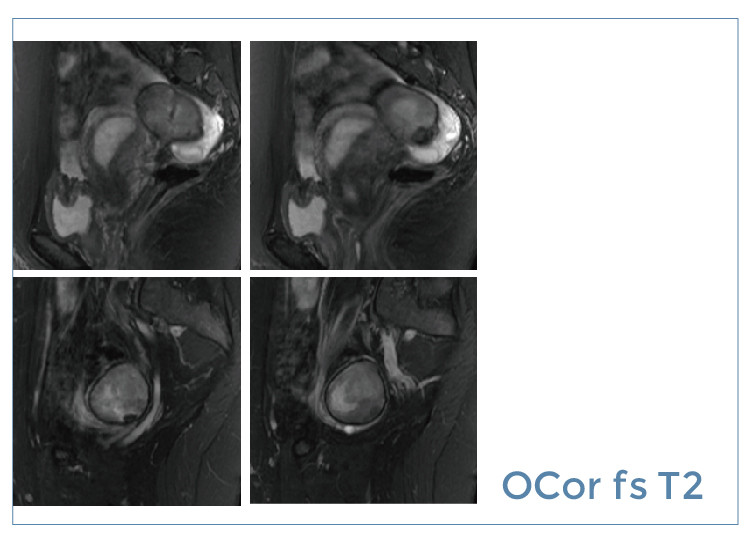

【朗润影像档案】磁共振影像病例分享(编号20190705)